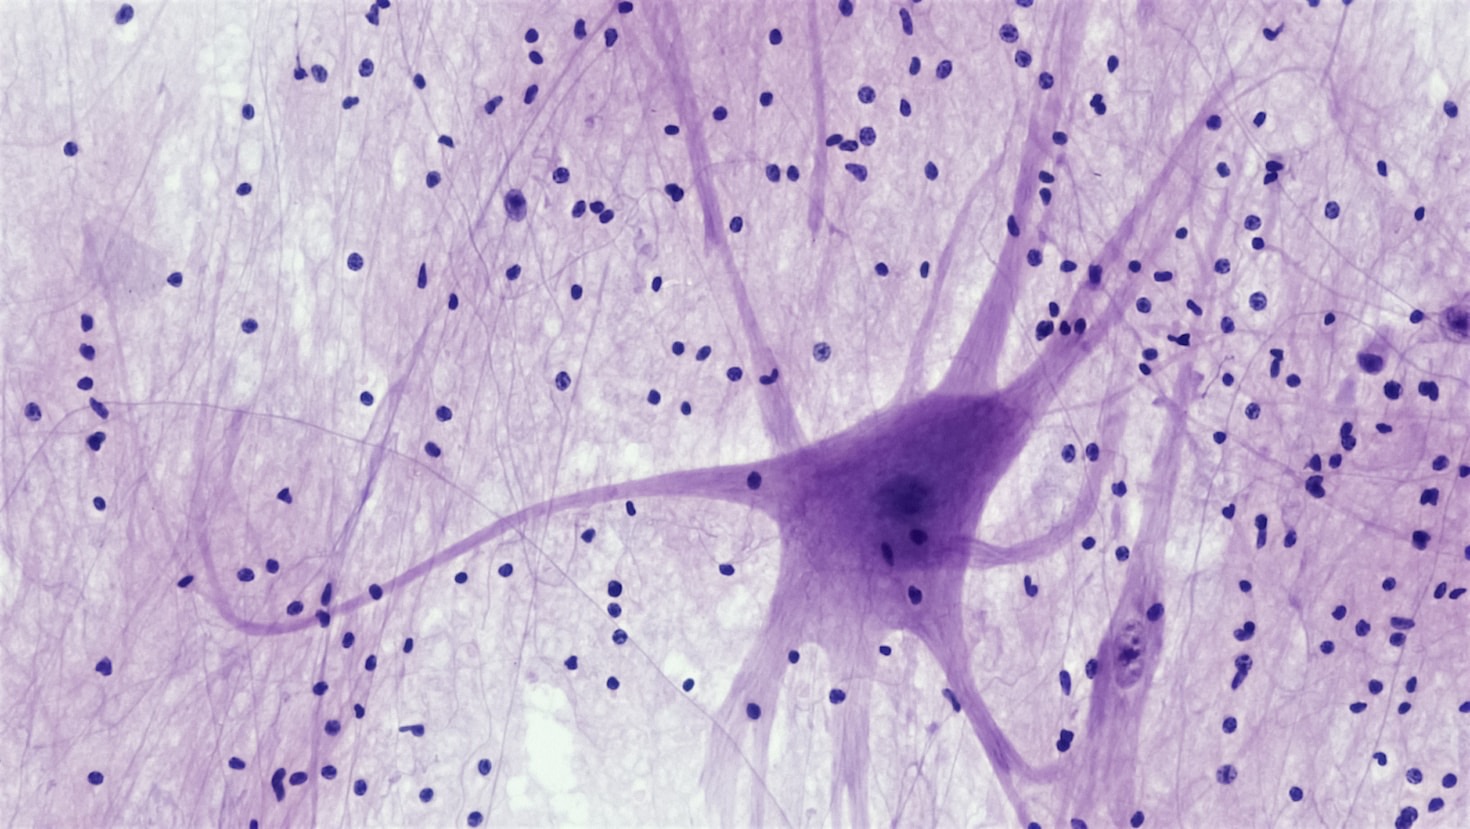

What is the Survival Identity Framework?

It’s a tool that reveals how your nervous system adapts to stress, helping you recognize your survival patterns.

Is this assessment based on personality traits?

No, it focuses on adaptive nervous system responses beyond traditional personality labels.

Understanding the Survival Strategies Your Nervous System Uses

Gain Clarity Beyond Labels

Learn how this framework moves past personality traits to reveal the adaptive responses shaping your behavior under stress.